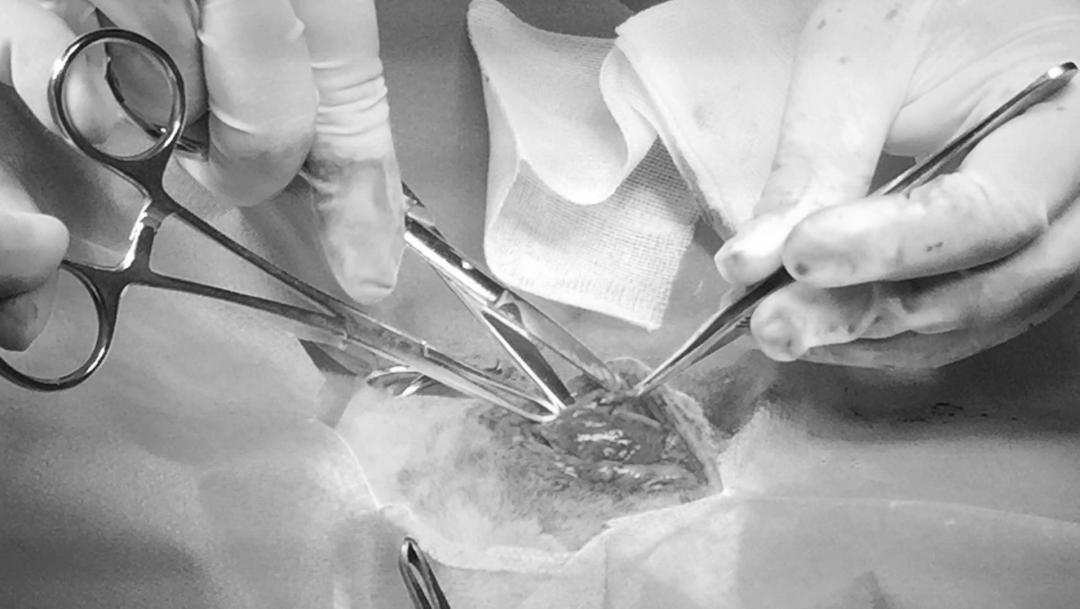

患有咽部黏液囊肿的动物常常会因为急性呼吸困难前来就医。分离时注意不要损伤神经,摘除腺体时牵拉导管要小心,避免造成人为导管破裂。摘除腺体一定要对发病腺体摘除干净(尤其是颌下腺和舌下腺一定要剥离到三叉神经的舌分叉处。

舌下腺与颌下腺共用同一个导管,摘除时必须将两个腺体同时摘除手术时遇到大的囊肿时,可以先将积液排除再摘除腺体,术后可能会造成血肿的形成,可以被机体自行吸收,不需要穿刺或引流。

发病腺体切除干净后,本病预后良好,注意术后可能会形成的血清肿,术后伤口感染。